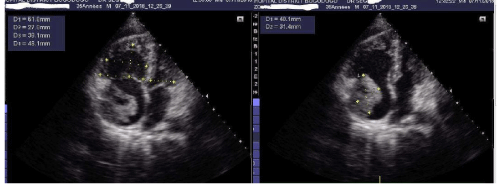

Delayed Rupture of Left Ventricular Aneurysm with Resultant Coexisting Pseudoaneurysm

Shwe Yee Oo1, Adel Ekladious2* and Yee Phyo Hein2

A 60 year old gentleman was transferred to a regional hospital following an admission for non-ST elevation myocardial infarction (NSTEMI) complicated by true left ventricular apical aneurysm and pyopericardium...